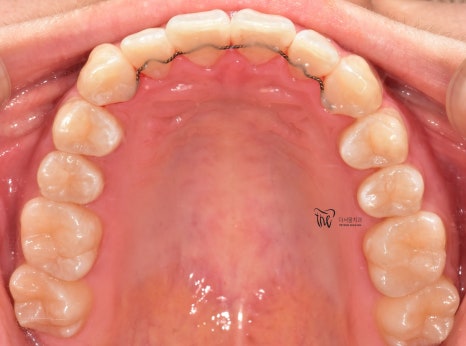

먼저, 임상 사진 5장을 보여드립니다.

그냥 겉으로 봤을 때는 단순 치아들의 불규칙성

때문에 치과에 내원을 하신 것으로 볼 수 있습니다.

조금씩, 치열이 가지런해지는 것을 볼 수 있으며

이미 여기 시점으로부터 어금니들이 서로

거꾸로 물리는 반대교합의 양상은 사라졌습니다.

치열이 고르게 바뀐거 뿐만이 아니라

앞니들이 많이 앞쪽으로 뻐드러졌던

모습의 변화를 함께 볼 수 있으며

처음에 오셨을 때와는 다르게,

구강 내 어금니들이 위, 아래로 서로 다

고르게 다 맞물릴 수 있도록 바뀐 모습 또한

한번에 보실 수 있습니다.